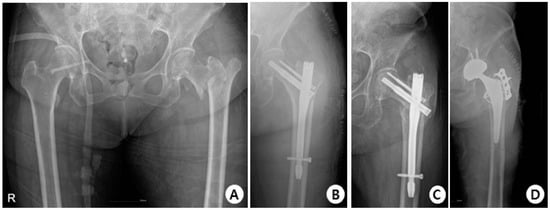

In terms of complications, in the GS group, there were 38 cases with no complications, 3 cases of cut-out (Figure 4), 1 case of non-union, and 1 case of delayed union.

Figure 4.

(A) Total hip AP X-ray of a 76-year-old female diagnosed with an intertrochanteric fracture of the left hip. (B) Immediately post-operation, the fractured segment was reduced in a slight valgus position using the GS hip nail implant. (C) The two months postoperative X-ray shows reduction loss and the progression of varus deformity, with the lag screw experiencing cut-out. (D) X-rays show the revision surgery performed with arthroplasty.

In the Affixus group, there were 34 cases with no complications, 5 cases of cut-out (Figure 5), 1 case of cut through, 4 cases of non-union, 1 case of delayed union, and 1 case of osteolysis.

Figure 5.

(A) Total hip AP X-ray of a 77-year-old female diagnosed with an intertrochanteric fracture of the left hip. (B) Immediately post-operation, reduction was performed using the Affixus hip fracture nail, but there appeared to be a mismatch in rotation. (C) The postoperative six-month X-ray shows reduction loss and the progression of varus deformity, with the lag screw experiencing cut-out. (D) X-rays show the revision surgery performed with arthroplasty.

There was no statistically significant difference in the occurrence of complications between the two groups, and neither group experienced implant breakage (Table 7).